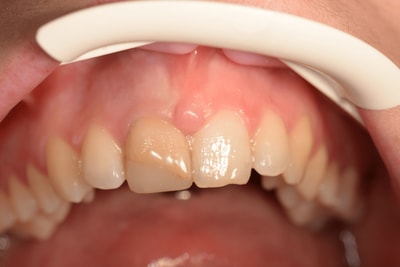

Les taches de l'émail

De nos jours, nous sommes de plus en plus confrontés à des tâches disgracieuses siégeant sur les dents antérieures. Les causes sont multiples. Que ce soient des fluoroses, des tâches blanches de l’émail, des tâches marrons , noires ou vertes, il faut savoir proposer, à notre patientèle, une solution simple et pérenne. En tenant compte des dernières évolutions scientifiques et industrielles, nous avons élaboré un protocole spécifique à chaque cas.